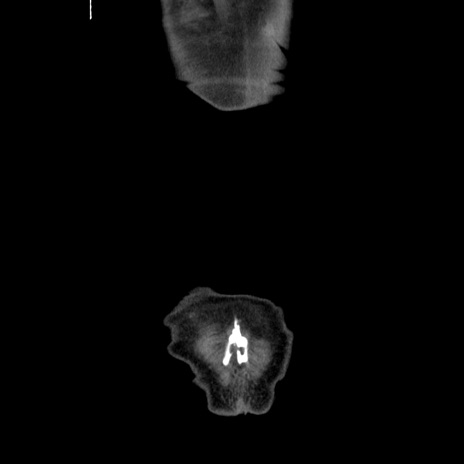

横断像

【症例】80歳代男性

【主訴】臍周囲痛

【現病歴】約6時間前から臍下部痛が出現。次第に腹部膨隆・背部痛も生じてきたため来院。背部痛の場所は変化しない。

【身体所見】意識清明、BT 36.3℃、BP  131/87mmHg、P 87bpm、SpO2 100%(RA)、臍周囲自発痛・圧痛あり、反跳痛なし、自発痛部位に一致して板状硬あり、腹部膨隆、腸雑音減弱、CVA tenderness両側陰性。

【データ】WBC 19600、CRP 0.33